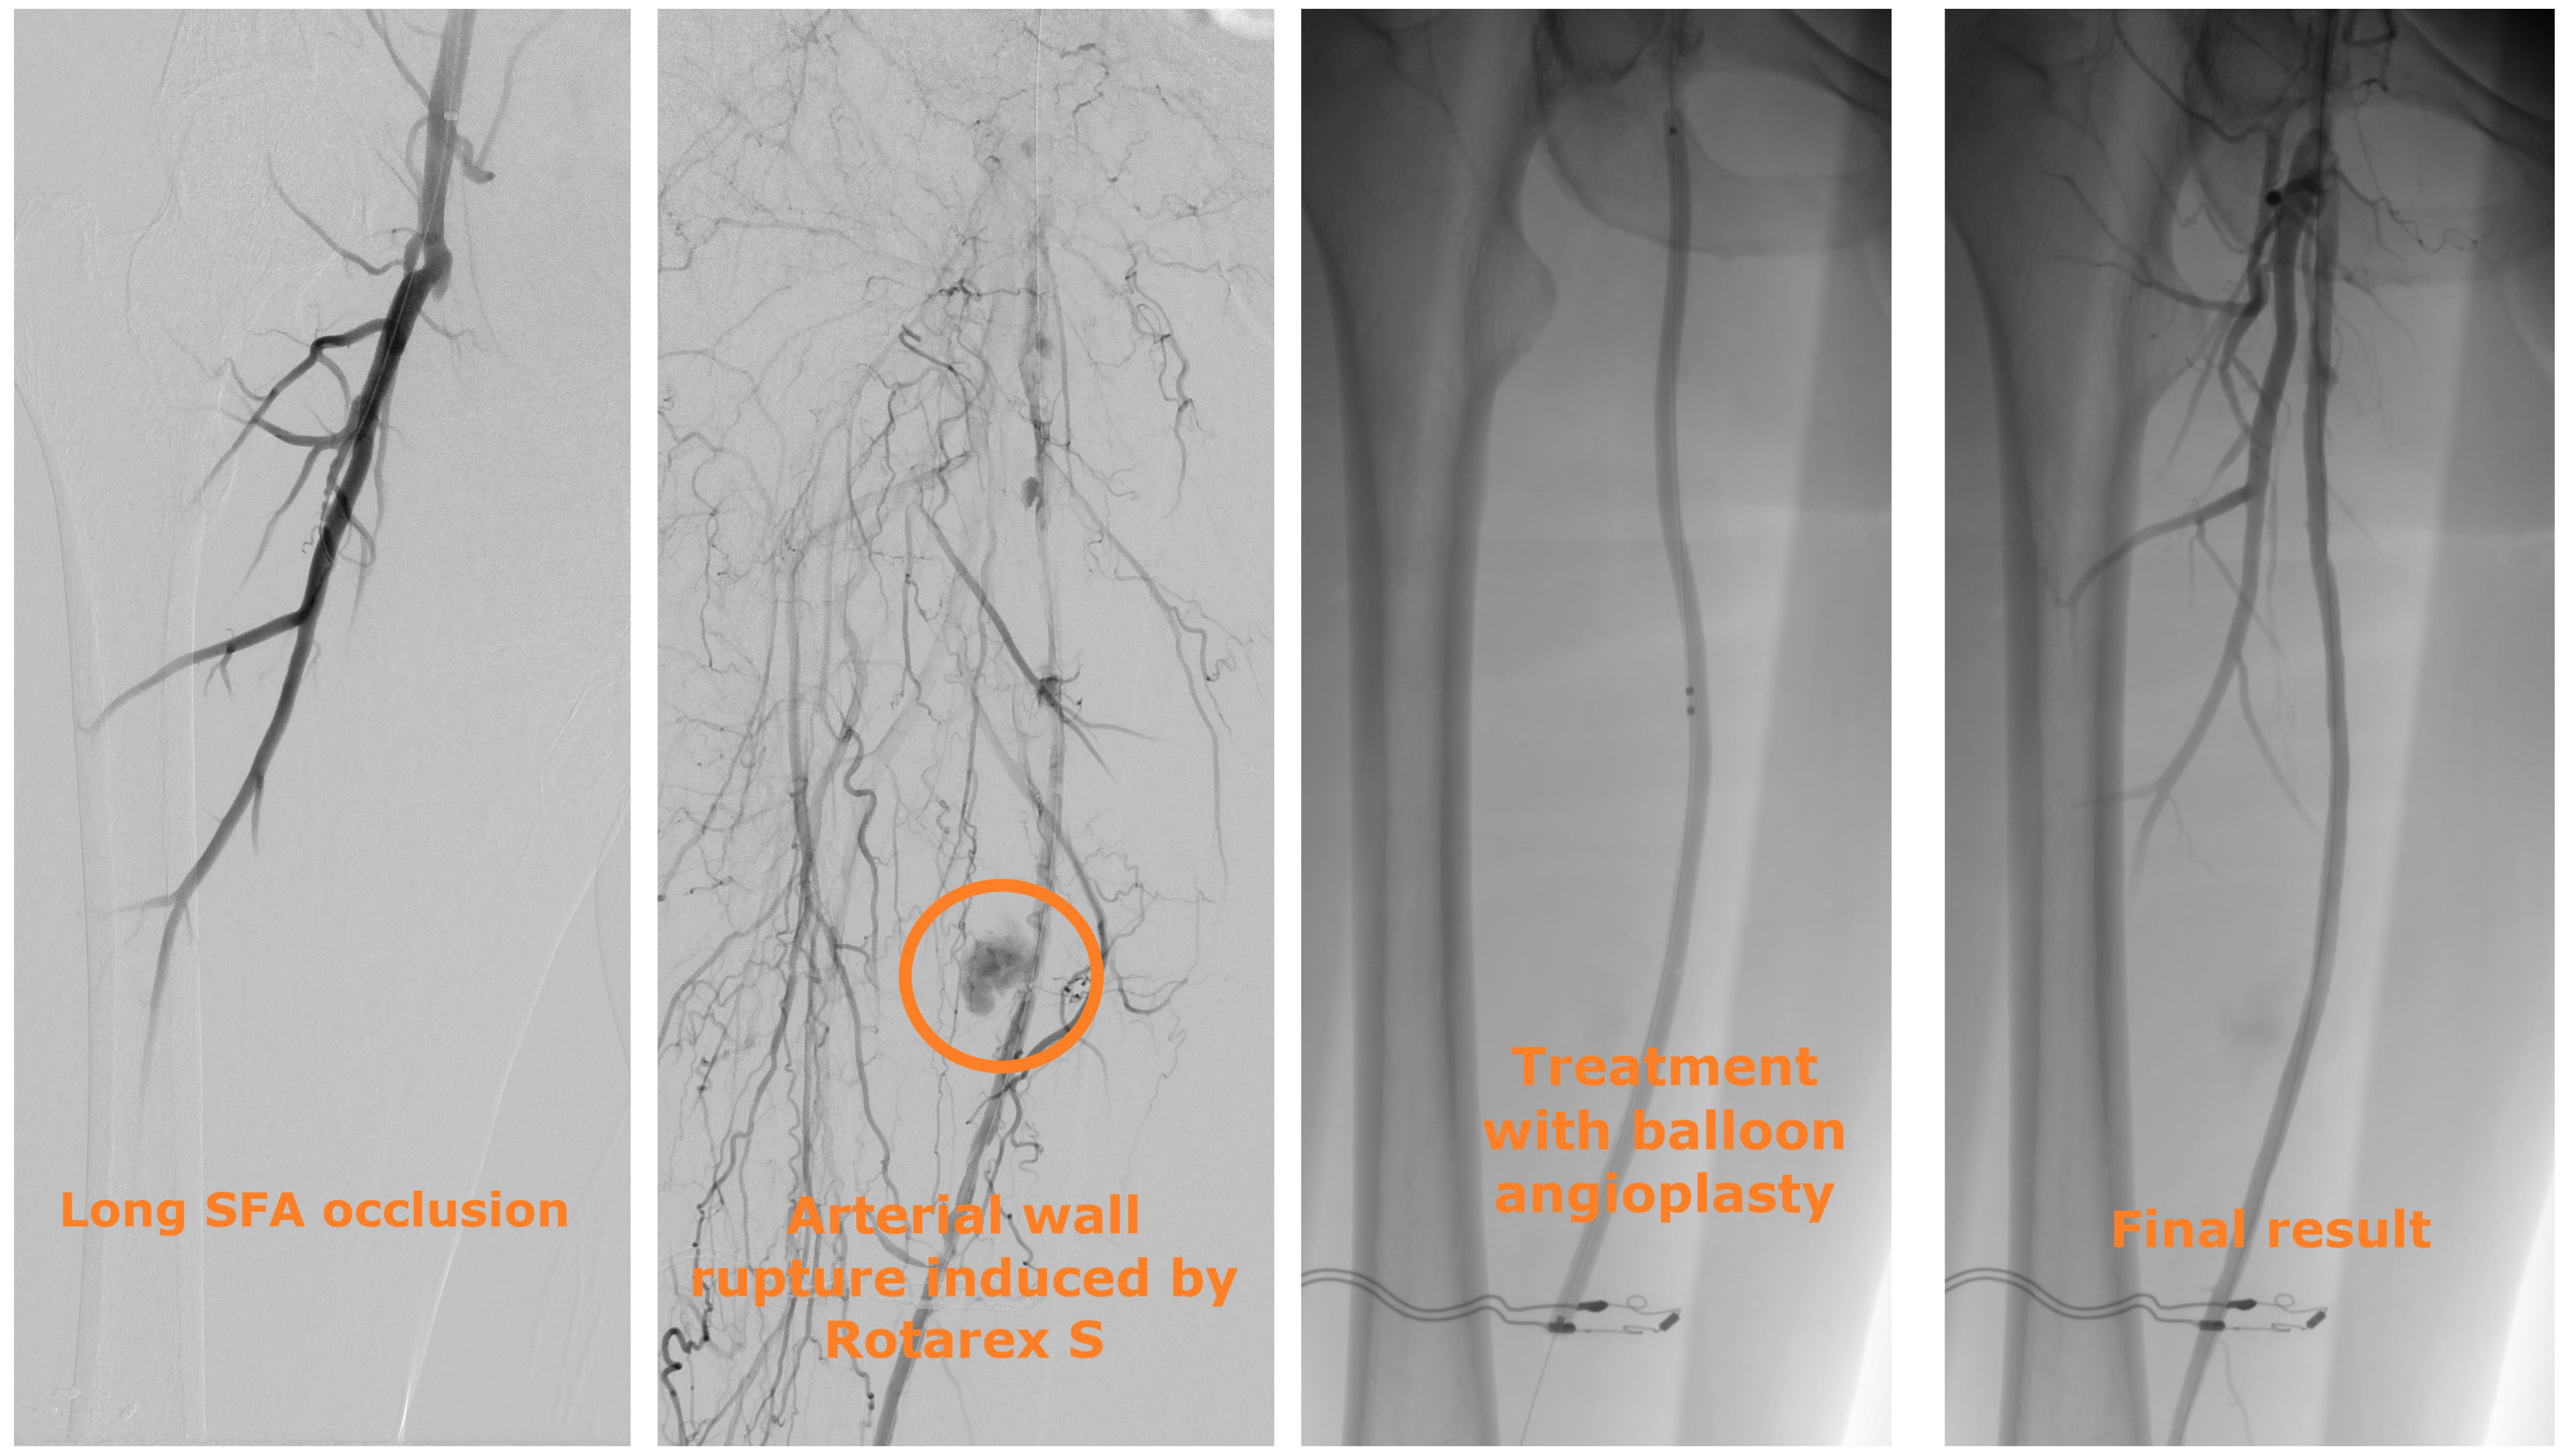

A 66-year-old woman presented with intermittent claudication in 1 calf (Rutherford classification stage 3). CTA highlighted total occlusion of the whole superficial femoral artery (Global Limb Anatomic Staging System grade 4).5 An atherothrombectomy device was used to prepare the target vessel (Figure 2). The control angiography revealed an arterial wall low-flow leak in the third part of the superficial femoral artery. Prolonged balloon dilation was performed to stop the bleeding. No stent was implanted.

When an arterial wall rupture induced by atherectomy occurs, the treatment is driven by the rupture characteristics; our treatment algorithm is shown in Figure 3. When the perforation is not associated with bleeding or is associated with low-flow bleeding, prolonged balloon angioplasty is typically sufficient. When the rupture is associated with high-flow bleeding, prompt deployment of a self-expandable covered stent is indicated.